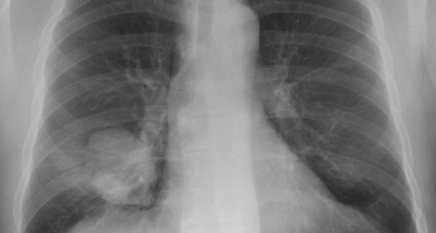

Unklarer Rundherd der Lunge und rezidivierendes Fieber. Diagnose, Komplikationen, Therapie und Verlauf.

Unklarer Rundherd der Lunge und rezidivierendes Fieber. Diagnose, Komplikationen, Therapie und Verlauf.